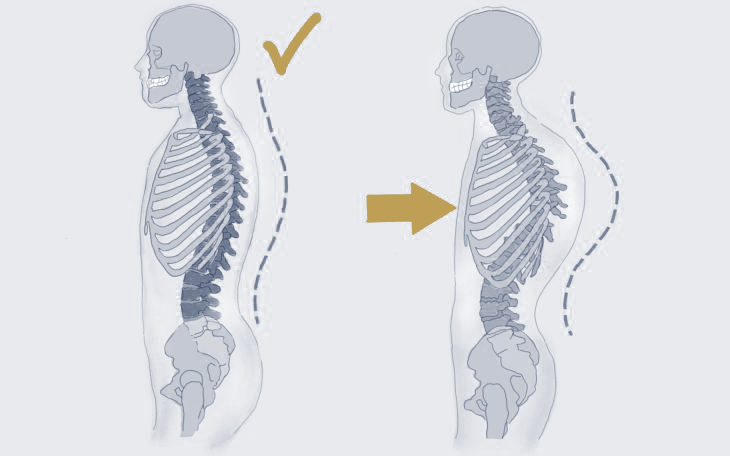

Der Begriff Skoliose bezeichnet eine S-förmige oder C-förmige Verkrümmung der Wirbelsäule in der Frontalebene (sichtbar bei Betrachtung von vorne). Kyphose beschreibt eine verstärkte Vorwärtskrümmung der Wirbelsäule in der Sagittalebene (sichtbar bei Betrachtung von der Seite).

Diese Fehlstellungen können sich im Erwachsenenalter entwickeln oder bereits seit der Kindheit bestehen und sich im Laufe der Zeit verschlechtern. Leichte Krümmungen verursachen oft keine oder nur geringe Beschwerden. Fortschreitende Verkrümmungen hingegen – insbesondere in Verbindung mit anderen Rückenleiden – können starke Schmerzen und Einschränkungen verursachen.

Kyphosen entstehen häufig durch osteoporotische Wirbelkörperbrüche. Weitere Ursachen sind degenerative Veränderungen (z. B. Spondylose), Operationen, Morbus Scheuermann oder Fehlhaltungen. Auch angeborene Fehlbildungen, Beinlängendifferenzen oder Erkrankungen wie Polio können Skoliose oder Kyphose verursachen.

Symptome